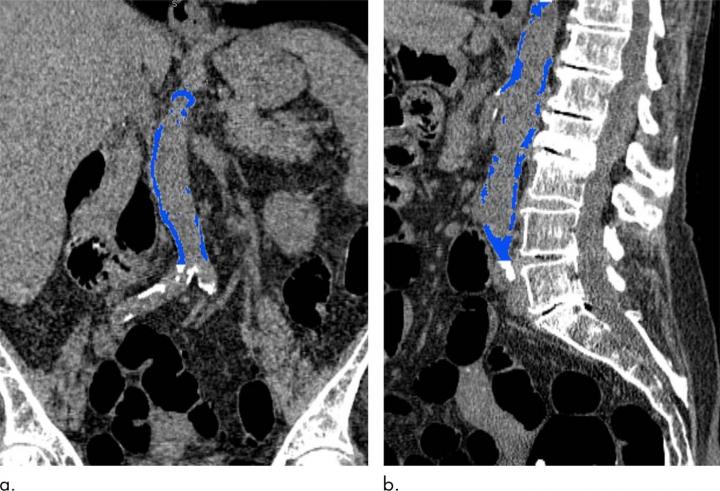

CT can also measure calcium in the abdominal aorta, the large vessel that carries oxygenated blood to the lower extremities. The abdominal aorta can be seen on abdominal imaging exams like CT colonography, also known as virtual colonoscopy, and in the diagnostic workup for acute cholecystitis, an inflammation of the gallbladder often caused by gallstones.

For the new study, conducted at the University of Wisconsin School of Medicine and Public Health in Madison, researchers assessed the relationship between abdominal aortic calcification on CT and cardiovascular events in 829 asymptomatic patients with a mean age of approximately 58 years. The patients had undergone nonenhanced screening CT colonography between April 2004 and March 2005. The researchers were able to follow the patients for an average of 11 years to see if they had developed adverse cardiovascular events like heart attack, stroke, death or congestive heart failure.

Of the 829 patients, 156 (18.8 percent) had a major cardiovascular event. The events occurred almost seven years after CT, on average, and included heart attack in 39 and death in 79. CT-based abdominal aortic calcification was a strong predictor of future cardiovascular events, outperforming the Framingham risk score. Abdominal aortic calcification was more than five times higher, on average, among those who had a cardiovascular event than those who didn't.

The results point to the potential of abdominal aortic calcification assessment as an opportunistic screening tool--something that could be added to other exams without the need for additional patient time or radiation dose. Patients could be assigned to preventive treatment regimens based on their cardiovascular risk categories.